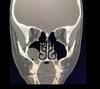

Estudio de imagen que se solicita para sinusitis

Tomografía de nariz y senos paranasales

*Gold standard

En que px se indica la TC para sinusitis

Oncológicos, inmunosuprimidos y sinusitis crónica